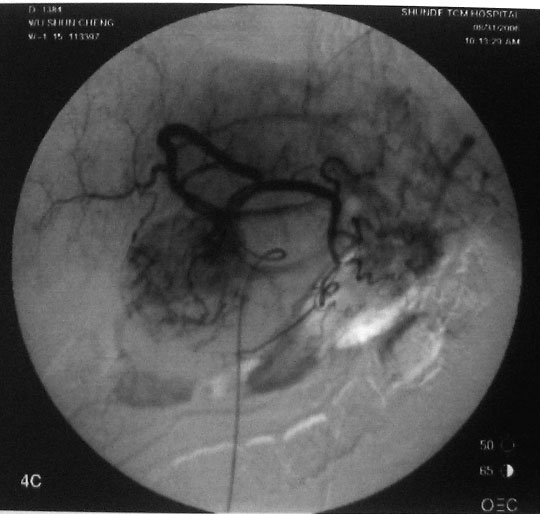

介入治疗过程:右股动脉穿刺,引入导丝导管,超选入肝固有动脉,造影显示肝右动脉肿瘤供血,圆球样肿瘤边界清楚。采用同轴导管进一步超选入右肝动脉、肿瘤血管边缘,注入化疗药+碘油混合剂7ml。

图4:栓塞治疗后,肿瘤已为化疗药+碘油混合剂充填。